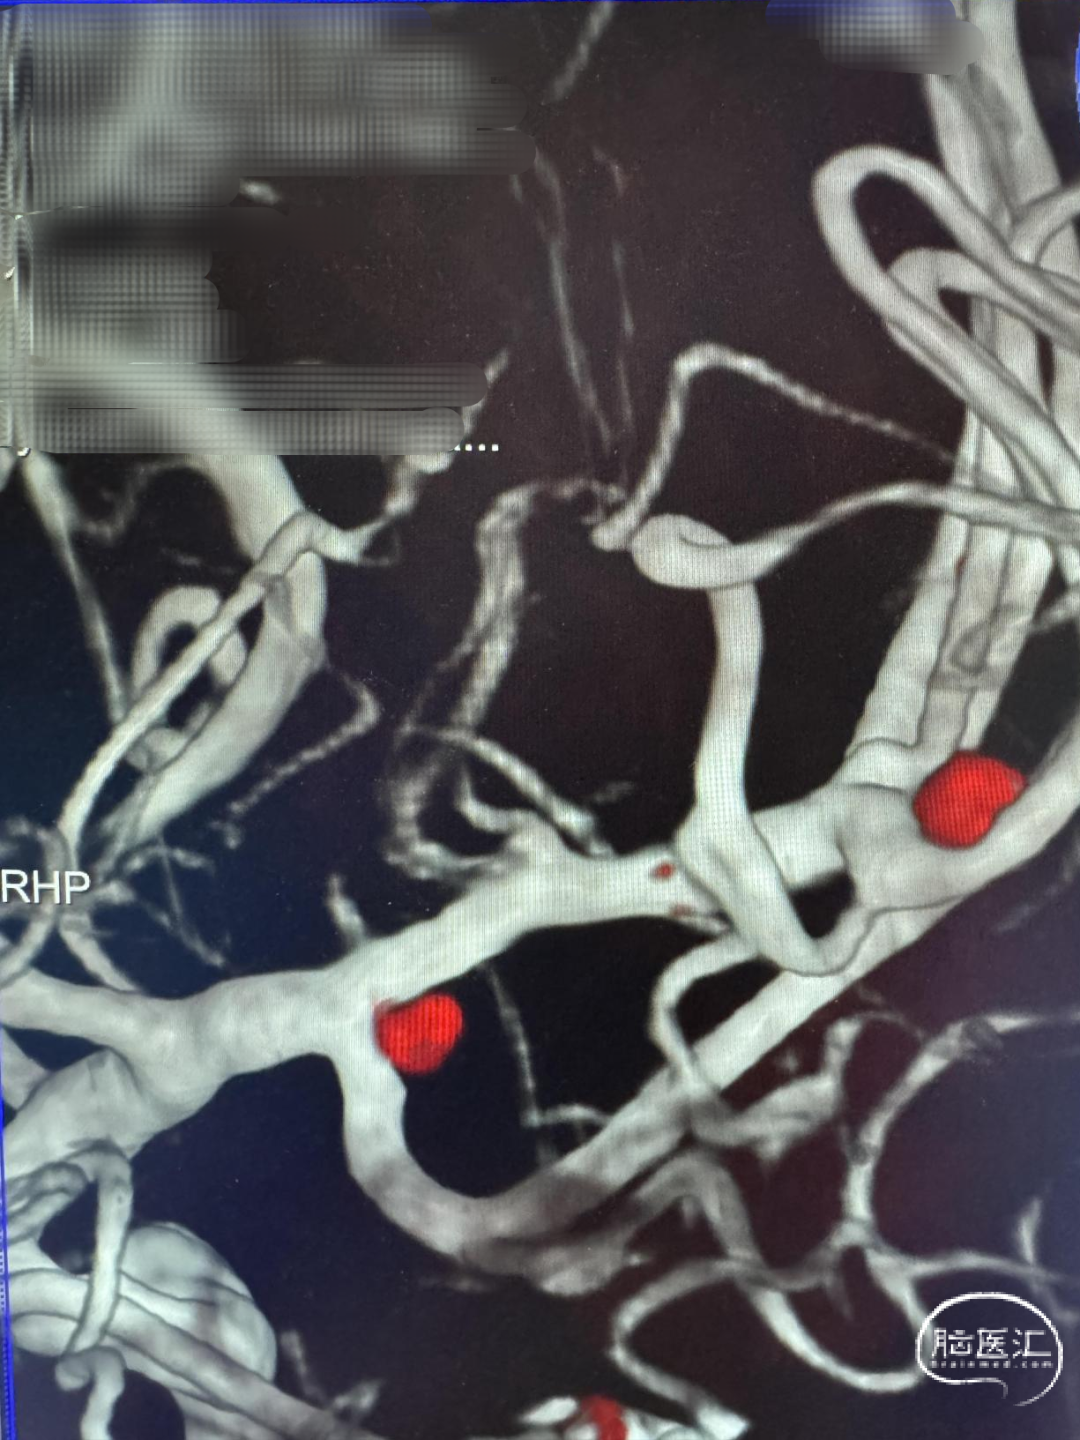

急诊头颅CTA:左侧大脑中动脉M1远端分叉处动脉瘤,左侧大脑中动脉M1段颞干分叉处动脉瘤。

左侧大脑中动脉M1段颞干分叉处动脉瘤

左侧大脑中动脉M1远端分叉处动脉瘤

方案1:考虑M1远端分叉处动脉瘤为破裂动脉瘤,支架辅助弹簧圈栓塞,二期处理颞干处动脉瘤。

方案2:同期处理,M1分叉处动脉瘤支架辅助弹簧圈栓塞;颞干处动脉瘤支架摆入颞干辅助弹簧圈栓塞。

方案3:M1分叉处动脉瘤支架辅助弹簧圈栓塞;颞干处动脉瘤单纯弹簧圈栓塞。